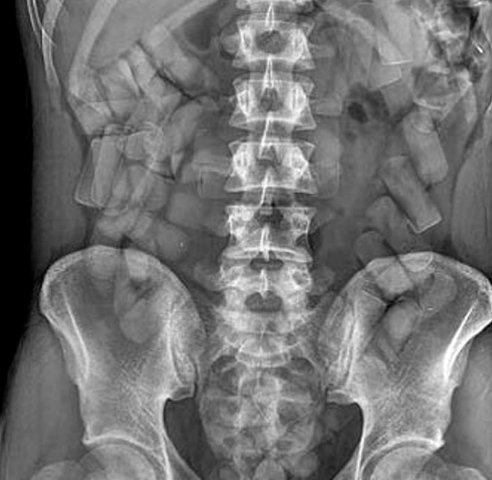

Da una lastra, i medici del San Biagio di Domodossola hanno potuto confermare il sospetto dei militari, refertando la presenza di numerosi corpi estranei nell’addome dell'uomo. Arrestato e piantonato in ospedale fino a completa evacuazione degli ovuli, l'uomo ha espulso 88 ovuli per un totale di 470 grammi circa di hashish. L'uomo, un anno fa, era stato fermato dalla Polizia di Stato a Susa nel Torinese mentre, a bordo di un furgone proveniente dalla Spagna, cercava di importare un chilo di droga.